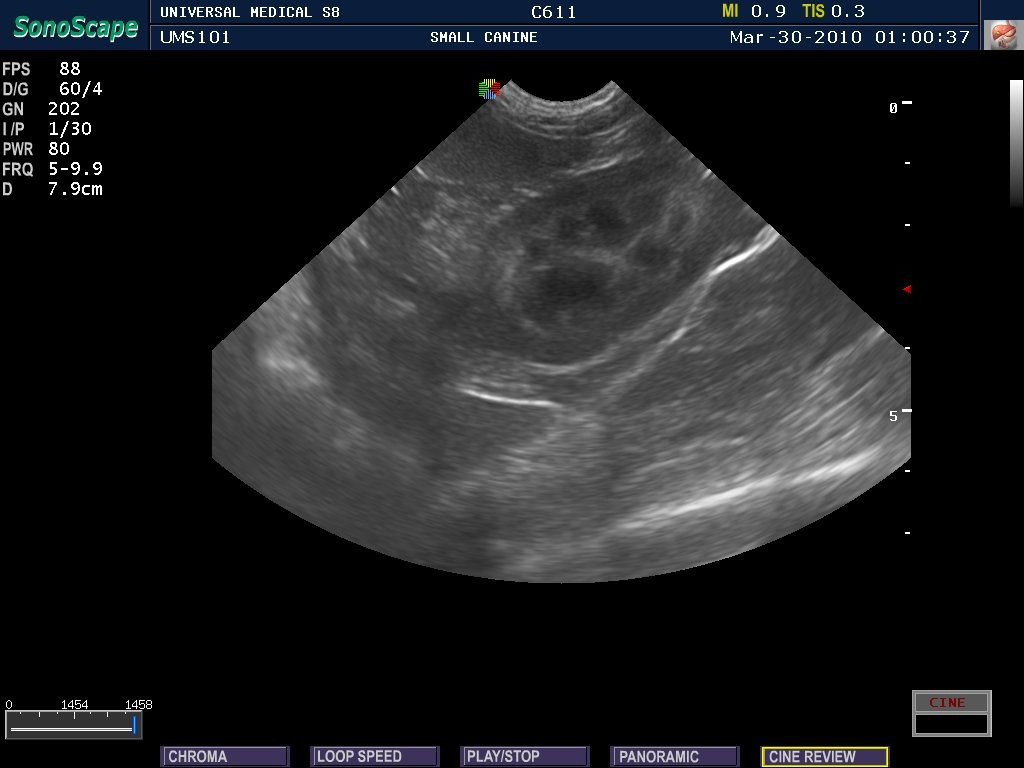

All Creatures Veterinary Clinic is equipped with ultrasound, a diagnostic tool that enables us to provide a higher level of care to our patients. While x-rays provide us with good images of bone, an ultrasound is the best way to identify problems with internal organs and soft tissue.

Ultrasound is an extremely useful, non-invasive diagnostic instrument that produces clear, easy to read images that are more detailed than an x-ray. The ultrasound allows our experienced veterinarian to visualize the internal organs and other structures inside the body and help find any abnormalities that cannot be seen or felt during a physical examination. It is used most often to diagnose bladder and kidney stones, discover abdominal masses, to aid in the assessment of organ function, and to evaluate pregnancies.

Providing this service in-house enables us to get you immediate results and provide treatment without delays caused by referring patients out to other hospitals. Pets are always sedated for this procedure making it a stress-free experience for them.